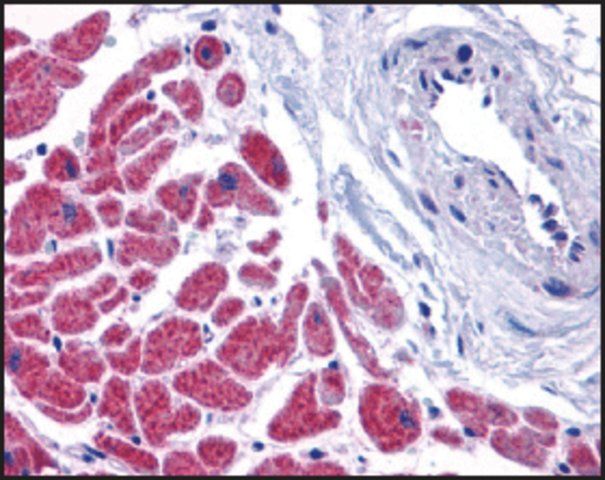

| technique(s) | immunofluorescence: 1:50-1:200 immunohistochemistry: 1:50-1:200 western blot: 1:500-1:2000 |